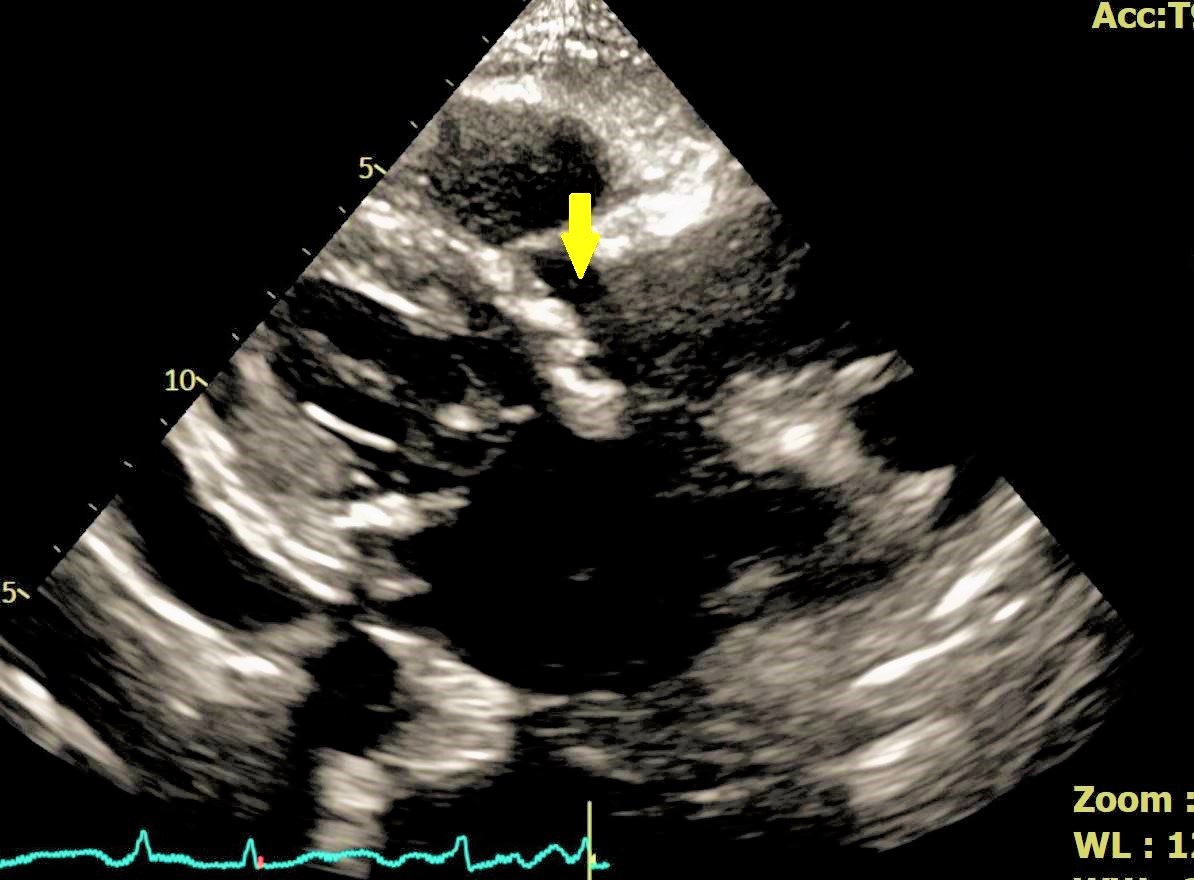

經心臟內科羅勖中醫師耐心詳盡的問診與檢查,發現該名婦人具有明顯心臟衰竭症狀,進一步安排心臟超音波檢查後,確診為「嚴重主動脈瓣膜狹窄」,屬於高齡族群常見且具高度風險的結構性心臟疾病;羅醫師指出,主動脈瓣膜狹窄會導致心臟無法有效將血液打出,進而引發肺水腫、呼吸困難、走路喘,嚴重時甚至可能導致休克。若未及時治療,重症患者一年內死亡率可高達五成。儘管患者年事已高,但羅醫師綜合評估其整體身體狀況、心臟衰竭嚴重程度後,認為其仍適合接受經導管主動脈瓣膜置換術(TAVR)。